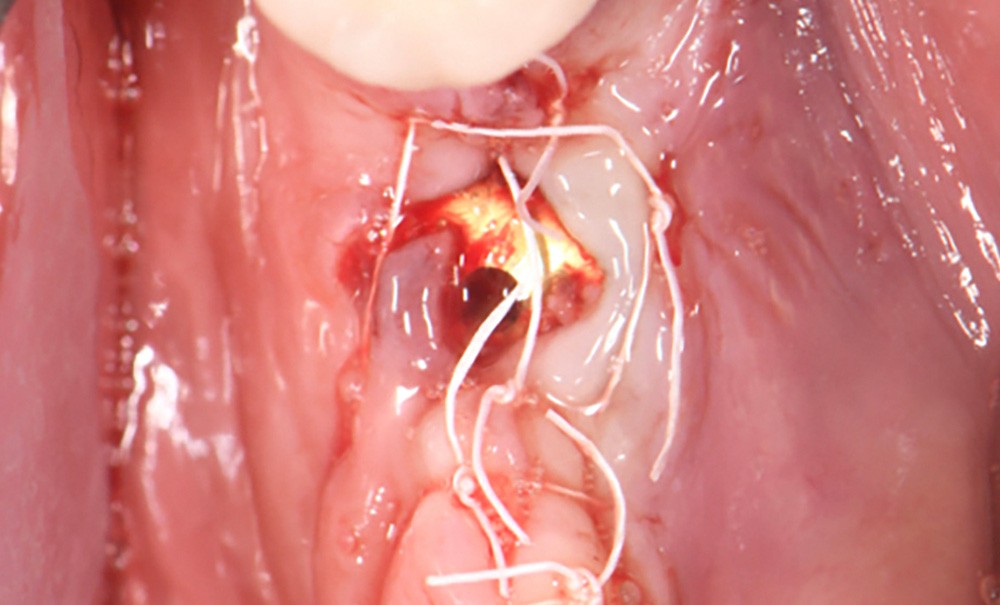

Actes préopératoires

La couronne a été déposée et une vis de couverture mise en place. La patiente a reçu un nettoyage supra-gingival général avec une attention particulière pour l’implant 47, et une irrigation locale avec du gel de chlorhexidine et du peroxyde d’hydrogène pour réduire l’inflammation des tissus. De l’amoxicilline (3 x 500 mg) a été prescrite, à commencer la veille de l’intervention chirurgicale.